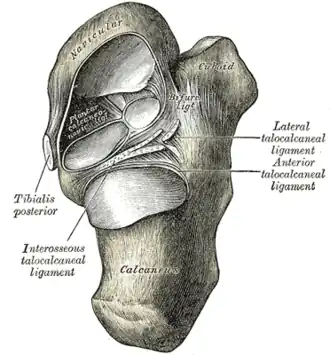

Navicular

The navicular, deriving its name from its boat–like shape, is a small but critical bone. It connects the ankle with the bones of the foot. It articulates with five tarsal bones (talus, cuboid, and three cuneiform bones) forming slightly mobile syndesmotic (fibrous) joints and has a significant function in maintaining the arch and the dynamic biomechanics of walking. The middle third of the bone lacks blood vessel penetration and it bears the majority of the load applied to the tarsal bones during weight bearing. Its vascular and biomechanical properties make it susceptible to injury. This may partly explain a higher risk of stress fractures and osteonecrosis in this location. Athletes who run, cut and pivot are particularly susceptible to injuries in this area. It is known as the keystone of the foot[10] and injuries to it can be "exasperating."[11]

Mueller–Weiss syndrome had been traditionally considered a spontaneous osteonecrosis of the navicular bone, but there is no certain pathogenetic explanation. Pathologic evidence of osteonecrosis (empty lacunae)[12] is seen in only a minority of pathological specimens.[13][14] It is frequently bilateral and associated with increased body mass.[7] Factors that have been thought to play a role include trauma, delayed ossification of the navicular and chronic biomechanical factors that put stress on the navicular.[15][7] Multiple pathogenetic theories have been proposed over the years.[8] Pathomechanic abnormalities involve shifting of the foot bones, which leads to a paradoxic flat foot, with a varus deformity instead of a valgus.[1] Multiple ligaments and the posterior tibial tendon attach to the navicular. These perform a significant function in acting as a dynamic stabilizer and maintaining bipedal biomechanics.[11]

Regardless of the exact cause, the pathogenesis of Mueller-Weiss syndrome is probably multifactorial and related to chronic loading on a suboptimally ossified navicular—a bone that is predisposed to central ischemia owing to its centripetal vascular perfusion arch.[11]